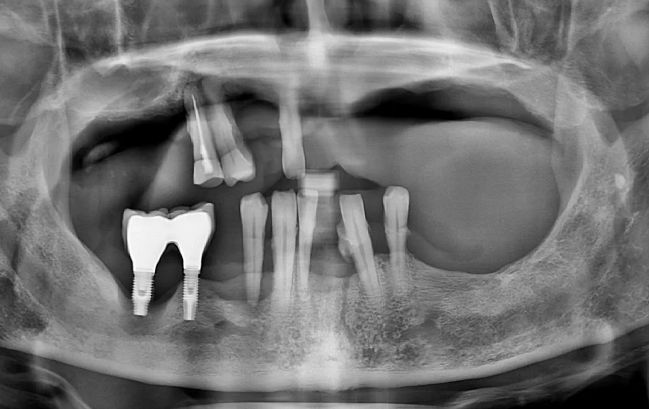

50대 남성, 원데이 앞니 임플란트